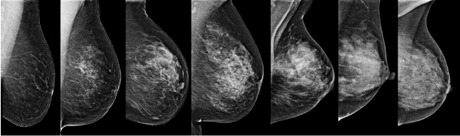

Examples of breast density patterns, with overall density increasing from left to right.

“Unfortunately the sensitivity of mammographic screening is seriously impaired in women with dense breasts. Fibroglandular and stromal tissue look equally bright as tumours on mammographic images. This causes tumours to remain masked for radiologists and thus breast cancer to remain undetected.”